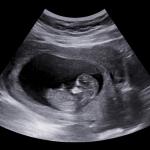

3 причина да правите секс в напреднала бременност

Непосредствено преди раждането, когато бебето вече се счита за доносено, специалистите препоръчват на бъдещите майки и татковци да правят секс. Така ще получите не само удоволствие, но и полза.